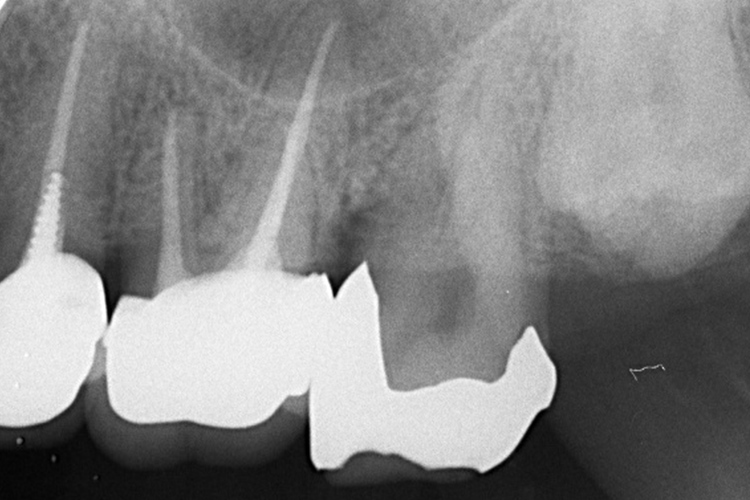

“実際の実施例2”

この患者様は、スケーリングより歯周ポケットが6mm以上ある患者様で患者様ご本人も歯周病になりかけている自覚がありました。また、口臭も気になされていましたので、ブルーラジカルの適用症例と判断し、施術を行いました。

(実施前)

施術前のレントゲンと口腔内写真です。施術前にプラークの除去を行ってから、施術します。